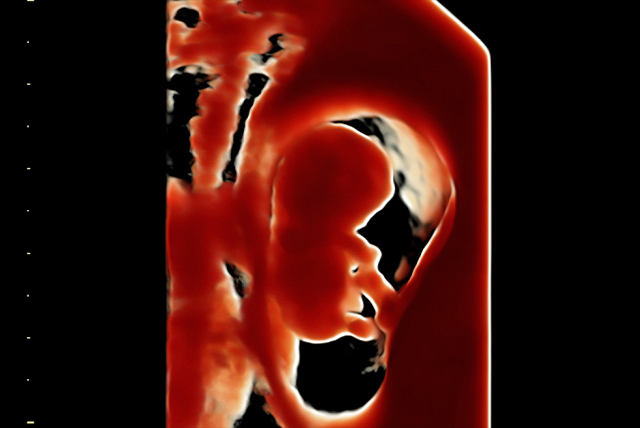

Advanced OBSTETRICS Imaging

✔️ First Trimester Scan

✔️ Evaluation of 12 weeks scan

✔️ Evaluation of NT and Ductus venous flow

✔️ Fetal growth scan 2D / 3D

✔️ Anomaly scan (4D scan)

✔️ Target Imaging for Fetal Anomalies (TIFFA)